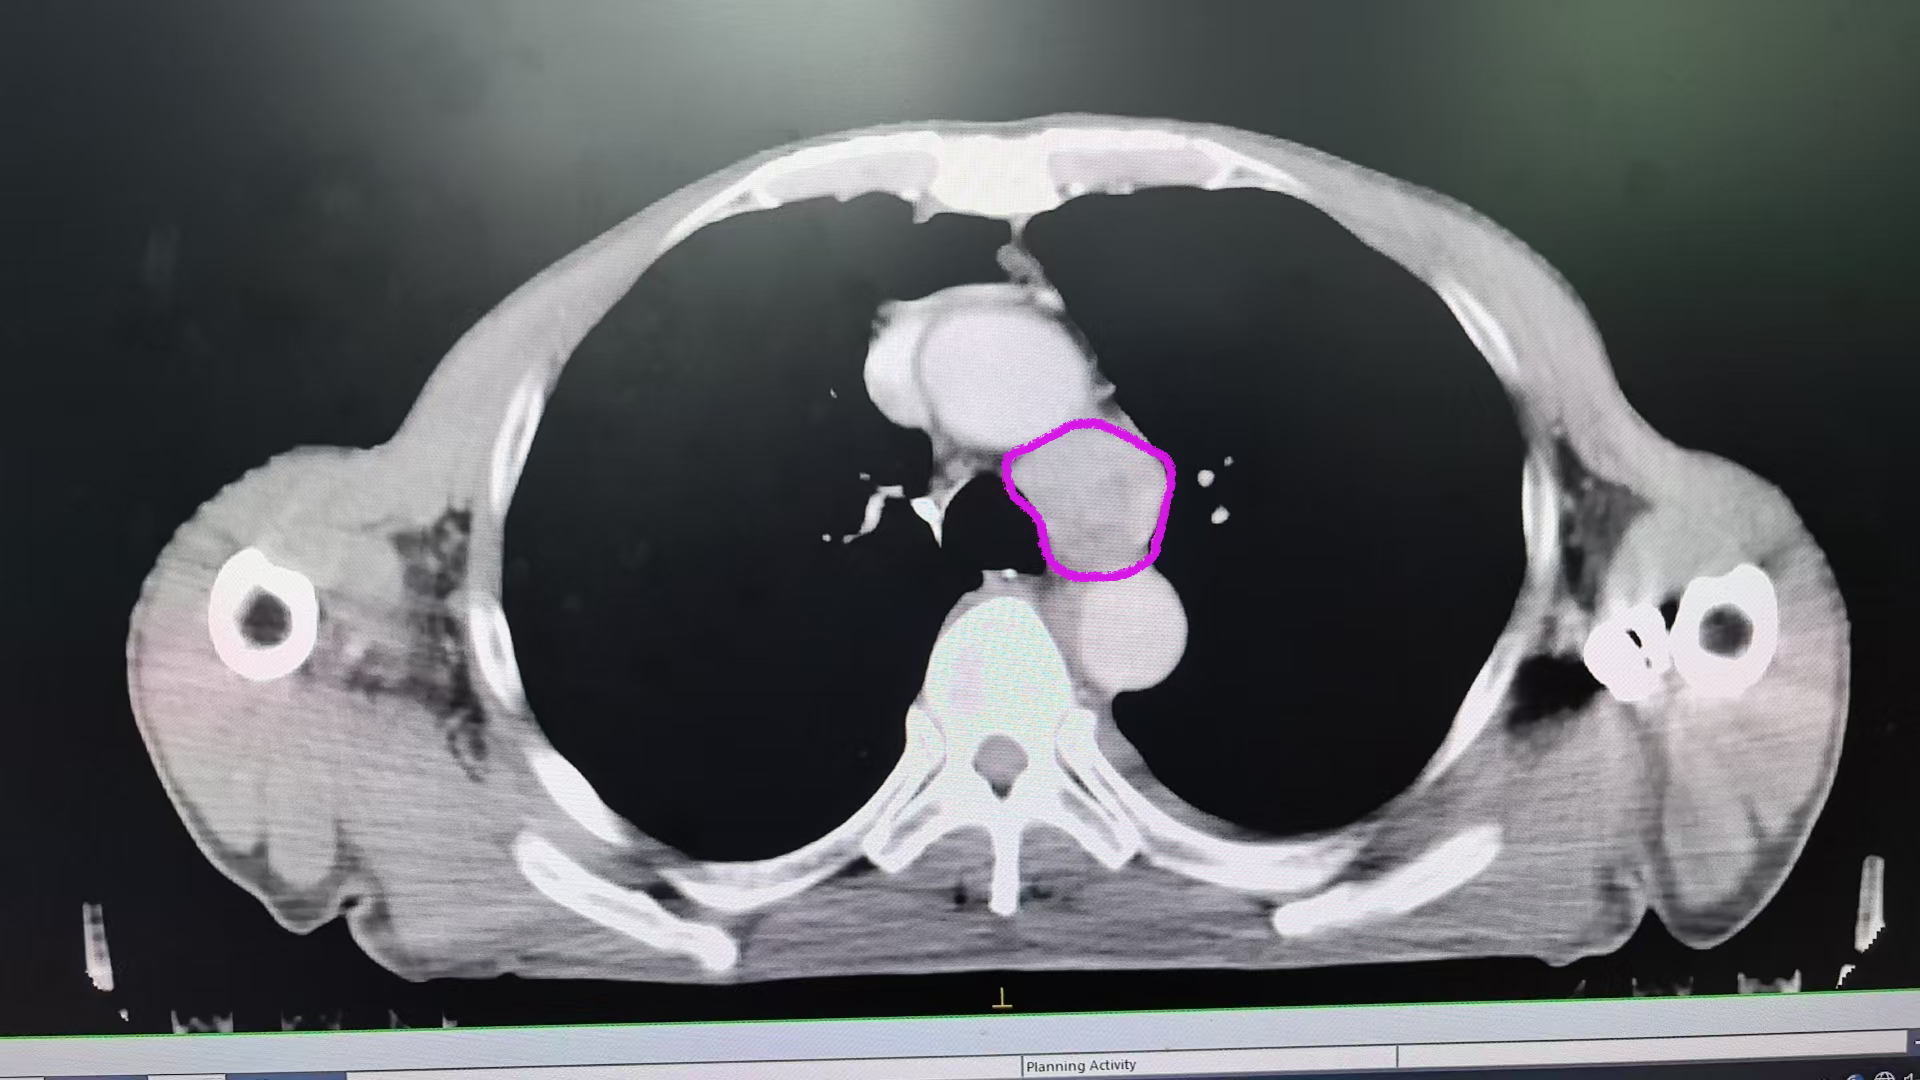

??在大眾普遍認(rèn)知里,食管癌一旦確診,大刀闊斧的外科手術(shù)往往被視為首要選擇。然而,對于部分特殊患者而言,傳統(tǒng)外科手術(shù)卻可能是難以逾越的“天塹”。?在食管癌的治療領(lǐng)域,內(nèi)鏡下全層切除手術(shù)作為一項極具創(chuàng)新性的技術(shù),正逐漸嶄露頭角。然而,這一手術(shù)的難度系數(shù)極高,對醫(yī)生的技術(shù)水平、經(jīng)驗積累以及醫(yī)院的綜合實力都有著近乎苛刻的要求。在眾多醫(yī)療工作者中,復(fù)旦大學(xué)附屬中山醫(yī)院內(nèi)鏡中心的鐘蕓詩教授,憑借其精湛的醫(yī)術(shù)和豐富的經(jīng)驗,在這一高難度手術(shù)領(lǐng)域取得了令人矚目的成就,成功為這類患者開辟出一條生命新通道,實現(xiàn)了既挽救生命又保留食管的雙重奇跡。??71歲的趙女士,命運的軌跡布滿坎坷。20年前,左側(cè)乳腺癌初次來襲,外科手術(shù)與放療的痛苦她咬牙扛過。此后,闌尾炎、肺結(jié)節(jié)、腸粘連伴小腸梗阻等病癥輪番折磨,多次手術(shù)讓她的身體愈發(fā)虛弱。10年高血壓病史,依靠纈沙坦控制血壓,生活剛稍有喘息,新的危機卻悄然降臨。??半年前,趙女士進(jìn)食時莫名出現(xiàn)哽噎感,飯后還偶有反酸、燒心,雖癥狀能自行緩解,卻像陰霾籠罩心頭。前往外院檢查,結(jié)果令人揪心:食管PET-CT檢查顯示食管上段FDG攝取增高,高度懷疑惡性腫瘤;胃鏡檢查發(fā)現(xiàn)食管隆起型糜爛,位置極為特殊,在距門齒18-22cm的高位食管處,病理確診為鱗狀上皮高級別瘤變并癌變;超聲內(nèi)鏡進(jìn)一步揭示,病灶處粘膜層增厚,部分與粘膜下層融合,甚至累及固有肌層。??面對這一診斷,當(dāng)?shù)蒯t(yī)院的醫(yī)生告訴她,就該病而言,傳統(tǒng)外科手術(shù)是常規(guī)治療手段,但趙女士的身體狀況卻讓這條路被徹底堵死。她體質(zhì)差,多次手術(shù)史及多種復(fù)雜合并癥,使她根本無法承受外科手術(shù)帶來的巨大創(chuàng)傷。就在趙女士幾乎陷入絕境之時,她的遠(yuǎn)房親戚帶給她了一線希望,向她推薦了器官保留專家復(fù)旦大學(xué)附屬中山醫(yī)院內(nèi)鏡中心副主任鐘蕓詩教授。她慕名來到復(fù)旦大學(xué)附屬中山醫(yī)院內(nèi)鏡中心,找到了鐘教授。??鐘蕓詩教授領(lǐng)銜的器官保留MDT團(tuán)隊,經(jīng)過全面、細(xì)致、嚴(yán)謹(jǐn)?shù)男g(shù)前評估,鑒于趙女士的特殊情況,團(tuán)隊制定了先化療及免疫治療的方案,如果治療有效,病灶退縮,再綜合評估是否有內(nèi)鏡下切除機會。兩個療程治療后,顯著效果令人振奮:CT復(fù)查顯示食管腫瘤明顯縮??;再次胃鏡復(fù)查,原病灶隆起消失,僅留不規(guī)則瘢痕樣改變,活檢病理提示炎癥改變,超聲內(nèi)鏡也顯示出腫瘤相關(guān)退縮的變化。此時,趙女士迫切希望可以通過內(nèi)鏡切除食管病灶。要知道,趙女士的病灶,在高位食管這個特殊位置,并且是疤痕樣改變,普通內(nèi)鏡下粘膜下剝離的方法,有可能對趙女士來說不能達(dá)到根治效果。種種要素,增加了手術(shù)難度,難度堪稱“在針尖上跳舞”。MDT團(tuán)隊再次討論后,鐘蕓詩教授憑借其精湛的內(nèi)鏡技術(shù),毅然決定挑戰(zhàn)這一高難度手術(shù),鐘教授決定為趙女士實施內(nèi)鏡下全層切除術(shù)。??鐘蕓詩教授作為復(fù)旦大學(xué)附屬中山醫(yī)院內(nèi)鏡中心的副主任,在消化內(nèi)鏡領(lǐng)域有著深厚的造詣和豐富的臨床經(jīng)驗。他長期致力于食管癌內(nèi)鏡下治療的研究和實踐,對內(nèi)鏡下全層切除手術(shù)有著獨到的見解和精湛的技術(shù)。在鐘蕓詩教授看來,內(nèi)鏡下全層切除手術(shù)不僅僅是一種技術(shù),更是一種對患者負(fù)責(zé)的態(tài)度,既要實現(xiàn)腫瘤的根治,又盡量減少創(chuàng)傷,在完整切除病灶的同時,最大限度保留食管功能、保留器官,患者術(shù)后恢復(fù)也快,生活質(zhì)量較高。鐘教授在手術(shù)前,會對患者的病情進(jìn)行全面、細(xì)致的評估,制定出最適合患者的手術(shù)方案;在手術(shù)過程中,他會憑借自己高超的技術(shù)和豐富的經(jīng)驗,小心翼翼地操作內(nèi)鏡,確保手術(shù)的安全和成功;在手術(shù)后,他還會密切關(guān)注患者的恢復(fù)情況,及時給予患者相應(yīng)的治療和指導(dǎo)。???復(fù)旦大學(xué)附屬中山醫(yī)院的內(nèi)鏡中心,患者迎來了關(guān)鍵的內(nèi)鏡切除手術(shù)——EFTR。手術(shù)過程中,鐘蕓詩教授展現(xiàn)出了卓越的技術(shù)優(yōu)勢。鐘教授結(jié)合放大內(nèi)鏡、超聲內(nèi)鏡,仔細(xì)觀察病變退縮范圍,精準(zhǔn)標(biāo)記切除區(qū)域,確保范圍大于殘余瘢痕,為徹底清除病灶奠定基礎(chǔ);緊接著,鐘教授沿標(biāo)記點在粘膜層和粘膜下層切開病灶邊緣,逐步切開并分離固有肌層,巧妙地分開肌層和外膜間隙,實現(xiàn)病灶的全層切除。最后,鐘教授用帶鼻固定線的全覆膜食管支架覆蓋創(chuàng)面。整個手術(shù)一氣呵成。術(shù)后病理結(jié)果更是令人欣喜:鱗狀上皮輕度異性增生,未查見腫瘤細(xì)胞,切緣陰性,手術(shù)大獲成功!后續(xù)鐘教授MDT團(tuán)隊繼續(xù)為趙女士制定免疫治療維持方案,如今她正常吃飯說話,生活質(zhì)量零影響。??目前這位患者,飲食、生活和患病前幾乎沒有太大區(qū)別,這一切都得益于鐘教授團(tuán)隊這種綜合的器官保留治療方案,成功達(dá)到了器官保留的目的,避免了傳統(tǒng)手術(shù)對身體的巨大創(chuàng)傷。正如鐘蕓詩教授所說,“而我們不僅要救命,更要讓患者有尊嚴(yán)地活著!我們追求的不只是腫瘤消失,更是患者重新綻放的笑容!”???復(fù)旦大學(xué)附屬中山醫(yī)院內(nèi)鏡中心鐘蕓詩教授團(tuán)隊,面對高位食管癌這一棘手難題,突破傳統(tǒng)治療局限,通過化療、免疫治療與內(nèi)鏡微創(chuàng)技術(shù)的精妙結(jié)合,成功解決了傳統(tǒng)外科手術(shù)無法攻克的困境。既避免了外科手術(shù)對患者身體的巨大創(chuàng)傷,又憑借高超內(nèi)鏡技術(shù)完美切除病灶,保住了患者的食管,維護(hù)了患者的生活質(zhì)量與尊嚴(yán)。這些成功案例,無疑為眾多身處絕境的食管癌患者點亮了希望之光,指引了新的求生方向。??隨著腫瘤免疫新時代的到來,免疫治療的加入,為術(shù)前新輔助治療在進(jìn)展期食管癌病人“器官保留”策略中的應(yīng)用,提供了充分的可行性。國內(nèi)外的多項研究證實,部分(30-40%)食管鱗癌病人在行新輔助放化療聯(lián)合免疫治療后,腫瘤能夠完全退縮,專業(yè)術(shù)語為“臨床完全緩解”。對于達(dá)到臨床完全緩解的食管癌病人,經(jīng)過內(nèi)鏡切除及病理評估后,若無腫瘤細(xì)胞殘留,僅需接受免疫維持治療。這樣做不僅能通過微創(chuàng)手段完全祛除病灶,降低治療后的復(fù)發(fā)率,還能夠在保存食管功能的同時保證長期生存質(zhì)量,這種治療策略即為“器官保留”策略。??當(dāng)然,并非所有的病人在接受新輔助治療后病灶都能完全退縮,但有研究表明,食管癌遵循了“肌層-黏膜下層-黏膜層”的退縮模式,即在多數(shù)病例中,殘留的腫瘤細(xì)胞位于食管黏膜層或黏膜下層,僅少部分腫瘤細(xì)胞留存于更深的肌層。此時內(nèi)鏡治療便發(fā)揮了其作用,不論是針對淺表病變的內(nèi)鏡下黏膜切除術(shù)(EMR)和內(nèi)鏡下黏膜下剝離術(shù)(ESD),還是適當(dāng)增加切除深度的內(nèi)鏡下全層切除術(shù)(EFTR),均可以做到病灶的完整切除,同時最大程度地保留了食管的結(jié)構(gòu)和功能。因此,鐘蕓詩教授的食管腫瘤MDT團(tuán)隊提出,如果在新輔助放化療聯(lián)合免疫治療后,對達(dá)到臨床完全緩解或近臨床完全緩解病人的初始腫瘤部位進(jìn)行完整內(nèi)鏡下切除,將會降低局部復(fù)發(fā)率,同時病人的長期生存率以及生活質(zhì)量將進(jìn)一步提高,從而達(dá)到“治愈腫瘤”與“保留器官”的兩全其美。??復(fù)旦大學(xué)附屬中山醫(yī)院內(nèi)鏡中心鐘蕓詩教授團(tuán)隊,對于新輔助放療、化療、免疫治療聯(lián)合內(nèi)鏡下切除術(shù),綜合治療食管癌,已經(jīng)積累了豐富的臨床經(jīng)驗。既免除了患者的手術(shù)之苦(不開刀),又保留了食管的完整性及正常生理功能,更重要的是患者的長期生存情況不受影響,生活質(zhì)量十分滿意。讓食管癌的病人保食管、保功能成為現(xiàn)實。專家介紹??鐘蕓詩教授,復(fù)旦大學(xué)附屬中山醫(yī)院內(nèi)鏡中心副主任,教授,博導(dǎo)。中國臨床腫瘤學(xué)會(CSCO)理事,中國抗癌協(xié)會消化道息肉及癌前病變專業(yè)委員會副主任委員,中國人體健康科技促進(jìn)會腸息肉防治專業(yè)委員會副主任委員,中國抗癌協(xié)會大腸癌專業(yè)委員會TEM學(xué)組副組長,中國醫(yī)師協(xié)會結(jié)直腸腫瘤專業(yè)委員會經(jīng)肛門微創(chuàng)手術(shù)專業(yè)學(xué)組、早診早治學(xué)組副組長,世界內(nèi)鏡醫(yī)師協(xié)會消化內(nèi)鏡微創(chuàng)聯(lián)盟理事長,中華消化內(nèi)鏡學(xué)會大腸鏡學(xué)組委員,上海市抗癌協(xié)會消化內(nèi)鏡專業(yè)委員會秘書長,上海市消化內(nèi)鏡學(xué)會委員兼任大腸鏡學(xué)組副組長。??主要從事消化道腫瘤的內(nèi)鏡治療和基礎(chǔ)研究。在國際上較早開展并熟練掌握包括ESD、EFTR、EUS、ERCP等各種內(nèi)鏡診療操作。專家門診時間:周一下午,周四上午